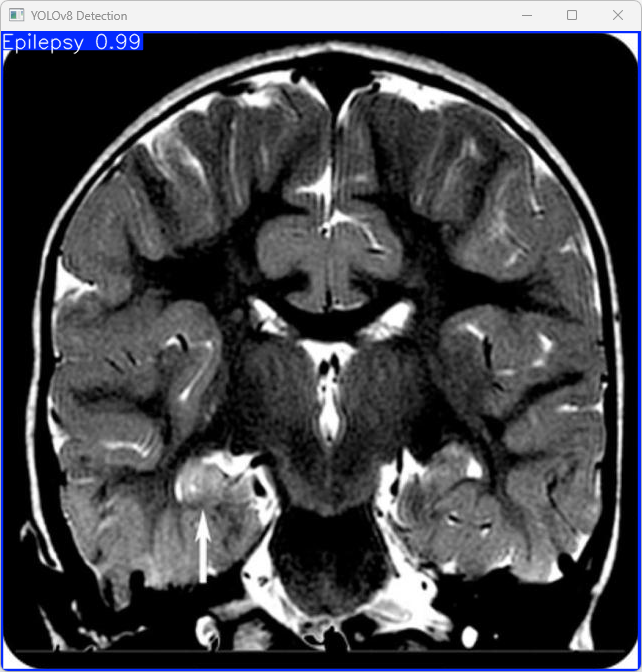

执行imgTest.py代码后,会将执行的结果直接标注在图片上,结果如下:

这段输出是基于YOLOv8模型对图片“imagetest.jpg”进行检测的结果,具体内容如下:

图像信息:

(1)处理的图像路径为:TestFiles/imagetest.jpg。

(2)图像尺寸为640×640像素。

检测结果:

(1)1个对象,并标记为“癫痫”(Epilepsy)。

处理速度:

(1)预处理时间: 3.4 毫秒

(2)推理时间: 5.1 毫秒

(3)后处理时间: 57.5 毫秒

总结:

该YOLOv8模型成功地对脑部疾病图像进行了分类,准确地识别出“癫痫”(Epilepsy)并提供了快速的推理和处理结果。